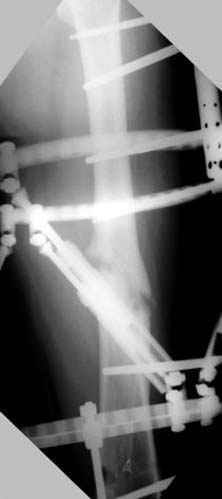

Отправитель: Djoldas Kuldjanov 23 Ноябрь 2004, 18:21

пластическая модель; и коррекция бедра аппаратом Илизарова.

Узкий к-м канал - тонкий гвоздь- усталостный перелом дистальных винтов - развитие нестабильности и как ее результат остеолиз вокруг гвоздя - деформация анатомической оси бедра. Похоже, что я понял почему аппарат, а не новый гвоздь:-)